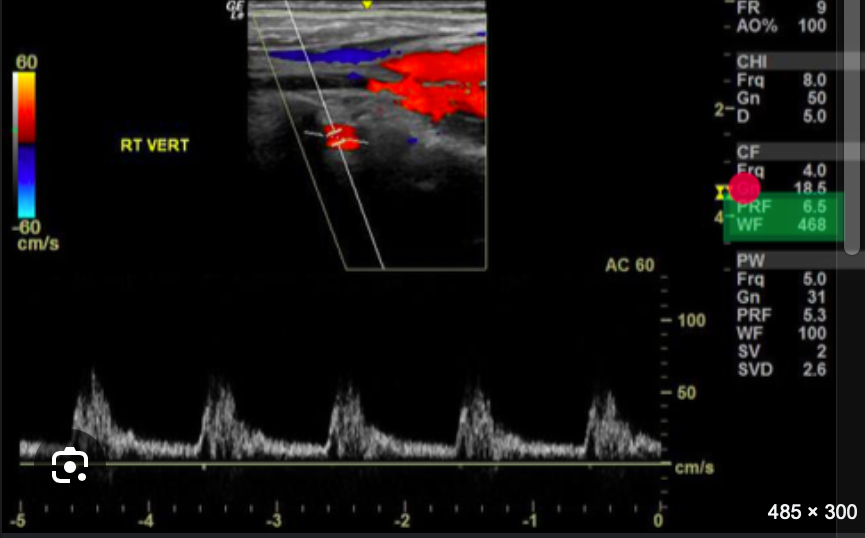

<p>Review the image and the system settings listed along the right side. Use your mouse to position your cursor over the settings that should be increased to improve the diagnostic quality of the color Doppler image. Click to set the cursor and confirm your answer.</p><p>.</p>

Review the image and the system settings listed along the right side. Use your mouse to position your cursor over the settings that should be increased to improve the diagnostic quality of the color Doppler image. Click to set the cursor and confirm your answer.

.

green.

<p>Review the image and the system settings listed along the right side. Use your mouse to position your cursor over the settings that should be increased to improve the diagnostic quality of the color Doppler image. Click to set the cursor and confirm your answer. </p><p></p>

green